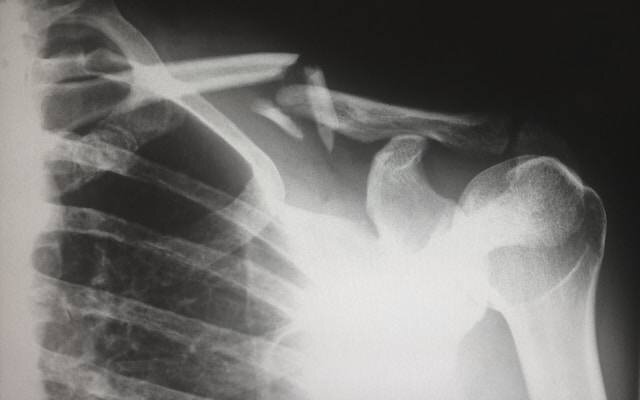

По словам Артюшкина, чаще всего ростовчане из-за гололёда ломают предплечья, лучевую и локтевую кости в нижней трети возле кисти. Это происходит при падении с выставленными руками.

«Получается закрытый перелом лучевой кости в типичном месте со смещением. Руки — это плата за то, что целыми останется голова, позвоночник, ноги», — пояснил терапевт. Чуть реже ломают плечевую кость, наружную и внутреннюю лодыжки с вывихом и без вывиха, копчик. Ещё реже — крестец и рёбра. Если случится перелом голени или бедра — это уже точно госпитализация и постельный режим в течение двух-трёх месяцев, подчеркнул эксперт.